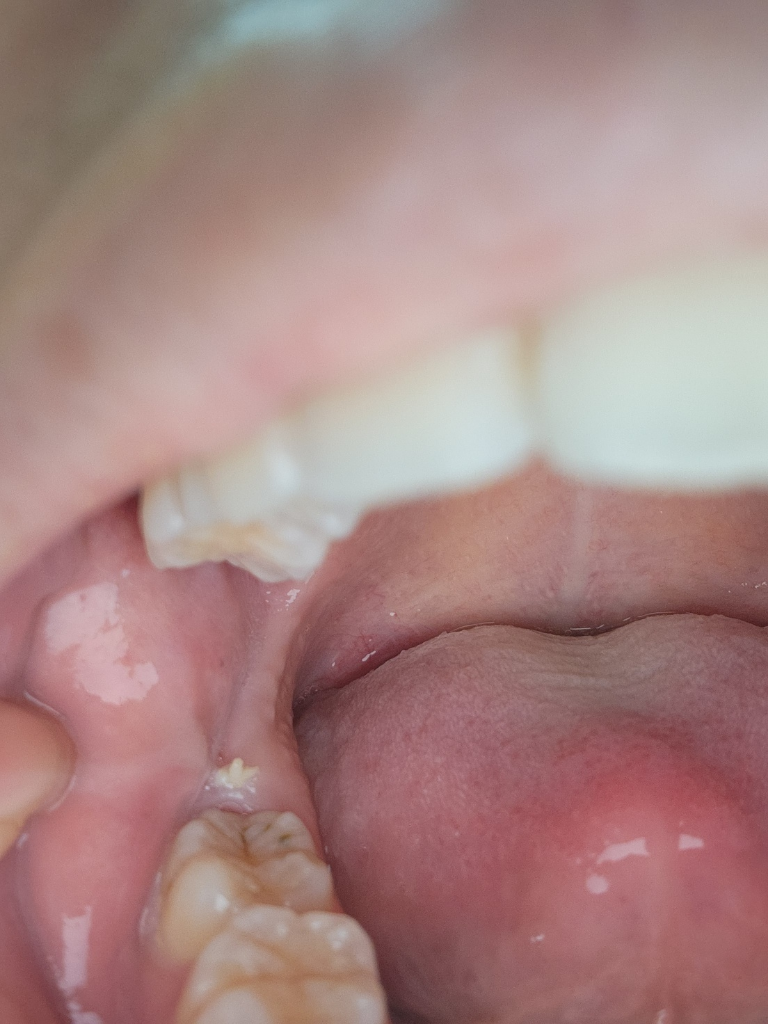

위의 사랑니가 아래로 내려와서 아래 잇몸을 누르게 된다면 해당 사진과 같이 하얀색으로 보이는 형태를 띨 수 있습니다. 이런 경우에는 내려온 사랑니를 발치하거나 잇몸을 자극하는 부위를 다듬어 줘야 할 수 있습니다. 자세한 확인을 위해서 치과에서 진료를 받아보세요

잇몸에 뭐가 난게 아니라 잇몸이 씹혀서 생긴자국이 아닐까 생각됩니다. 정확한건 치과에 가셔서 엑스레이 사진을 찍어보시는게 좋을것같습니다.

구내염이 생긴 것으로 보이며, 해당부위 염증개선을 위해 소독용 가글인 헥사메딘 가글액으로 가글하여 관리하길 권합니다. 만약 계속 커지는 경우에는 치과 진료를 받길 권합니다.